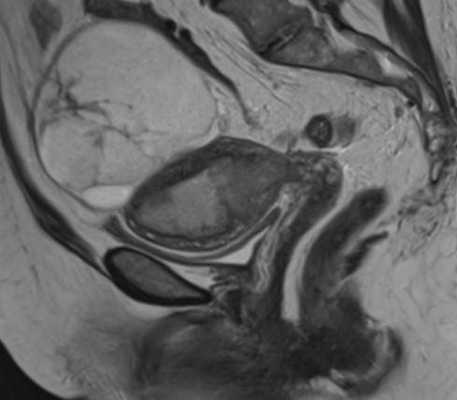

МРТ матки выполняют по показаниям в сложных диагностических случаях не ранее 4 месяца гестации. Дифференциальную диагностику миомы проводят с аденомиозом, раком и саркомой матки, полипами эндометрия, опухолями яичников, забрюшинными новообразованиями, трофобластической болезнью. При необходимости беременной назначают консультации уролога, онколога, хирурга.

- МРТ малого таза. Отражает точную топографию, размер и количество миоматозных узлов. Часто шеечная опухоль сочетается с миомами тела матки. Данные исследования используются при выборе тактики лечения.

Миомы в области матки составляют особую угрозу в ходе процесса вынашивания ребенка. Так, лейомиома может получить быстрый рост во время беременность в связи с изменением гормонально фона (повышение уровня эстрогенов в организме женщины). Миома шейки матки иногда приводит к нарушению кровоснабжения стенки. Миома в нижнем маточном сегменте повышает риск кровотечения и сложности выполнения кесаревого сечения. Миомная опухоль, расположенная за плацентой, может спровоцировать недостаточность и отслойку плаценты. Миомные образования в ходе беременности обычно выявляют с помощью УЗИ. МРТ здесь играет уточняющую роль, когда нужно дифференцировать миому с объемными образованиями яичников и уточнить источник болевого синдрома при геморрагической дегенерации узла.

Признаки миомы на МРТ

Диагностировать миому на МРТ не составляет особого труда. Врачи на томографических изображениях видят её в виде четко очерченного образования округлой формы. На магнитно-резонансных снимка определяется псевдокапсула миомы в виде тонкого ободка, гиперинтенсивного по Т2. По МР картине специалист может говорить о характере миомы, является ли она кистозной или миксоидной, лейомиомой или липолейомиомой. В зависимости от неоднородности миомы будут видны сопутствующие процессы - кровоизлияние, некроз, обызвествление.

Субсерозная миома на МР-сканировании

При магнитно-резонансной томографии получают множественные снимки анатомической зоны во фронтальной, сагиттальной и аксиальной плоскостях. Врач имеет возможность изучить каждый участок органа, выявить малейшие отклонения от нормы. Миоматозные узлы обычно выглядят на МР-сканах как округлые гипоинтенсивные образования разных размеров. Смена режимов позволяет выявить псевдокапсулу, оценить характер кровоснабжения опухолей.

Если на МРТ нашли миомные узлы, рентгенолог описывает локализацию, размеры, количество, тип образований. Врач может выявить кровоизлияния, очаги обызвествления и некроза. Сведения о новообразованиях специалист фиксирует в заключении. Результаты МРТ изучает клиницист. На основании выводов рентгенолога, гинеколог ставит окончательный диагноз и выбирает способ лечения.